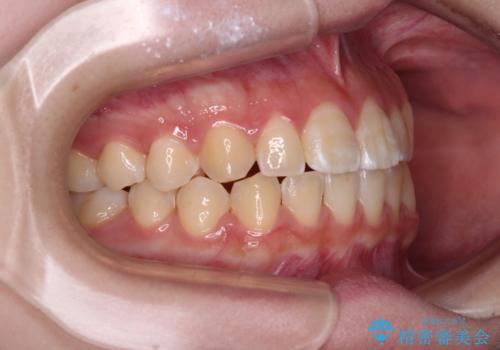

- 前歯のデコボコと磨きにくい奥歯を気にして来院された患者様です。

左右ともに上顎第二大臼歯が外側に転位しており、大変磨きにくくなっているため、補助装置により内側に引き込むことで改善することとしました。

外側を向いていた奥歯は比較的早い時期に歯列に収まり、咬み合わせも磨きやすさも改善することができました。

歯列は元々悪くなかったので、1年ほどで治療を終えることができました。